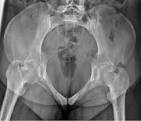

what view is this? what’s the tube angle?

pelvic inlet, 25-40° crawdad (ischial rami are perp to IR)

what view is this? tube angle

pelvic outlet , 30-45° cephy (ischial rami are parallel to IR)

what angle for both Judet hips (typical)

45°

Judet hip - iliac view

affected/unaffected side of the pelvis is rotated 45 degrees anteriorly, allowing visualization of the 1 and 2

1 - posterior column, 2 anterior wall and rim

Judet obturator view

unaffected/affected side of the pelvis is rotated 45 degrees anteriorly, allowing visualization of the 1 and 2

affected

obturator ring, posterior wall